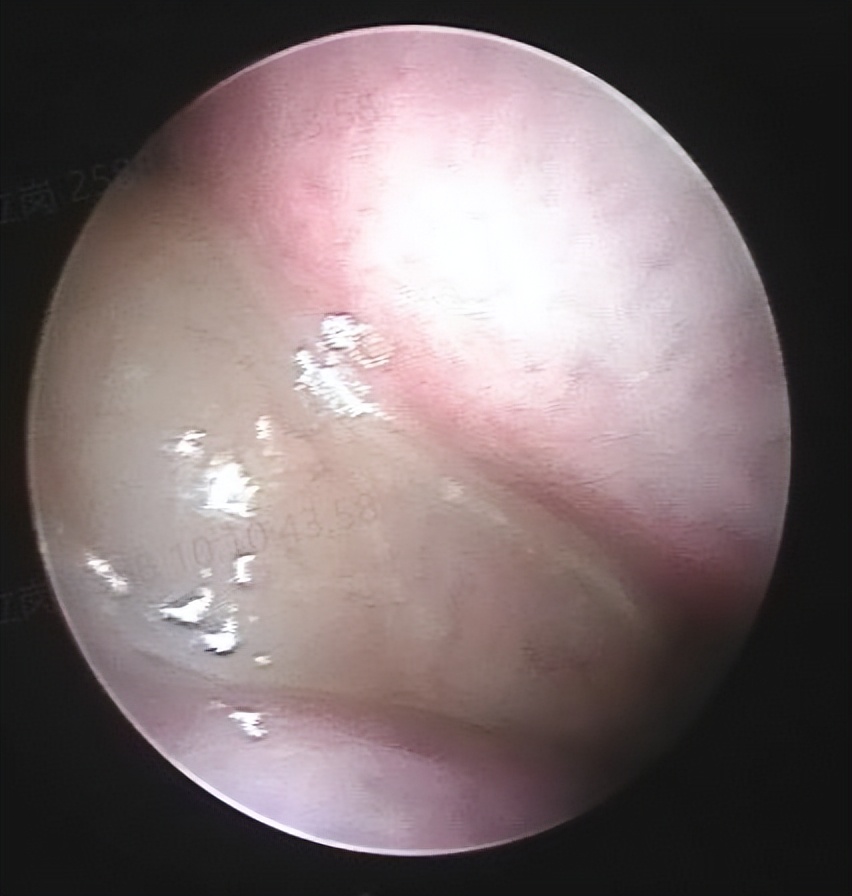

和家人商量后决定做手术治疗,就入院了。这次安排的是鼻内镜鼻窦炎微创手术和下鼻甲手术,插管全麻后就开始了手术。在鼻内镜下切除鼻息肉和开放鼻窦后,清除了炎症病变,并做了鼻甲的射频治疗,解决鼻炎的问题,整个的手术非常的顺利,用时约一个多小时。术后查房患者无明显的不适,无手术相关的并发症。